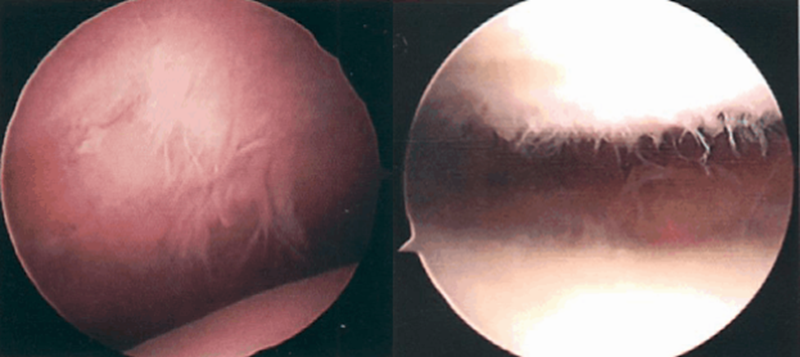

髌骨软化症Ⅲ级

髌骨软化症Ⅳ级

Ⅲ级:软骨的毛刷状或纤毛化改变达关节软骨厚度一半以上,直径>1.3cm,关节软骨表面类似蟹肉样改变,表面有多发软骨碎片附着其下的软骨。

Ⅳ级:关节软骨全层受侵,软骨下骨暴露,表现为进展期髌股关节炎。

Ⅰ~Ⅱ级为早期,主要保守治疗,Ⅲ~Ⅳ级为进展期,需要手术及关节镜治疗。